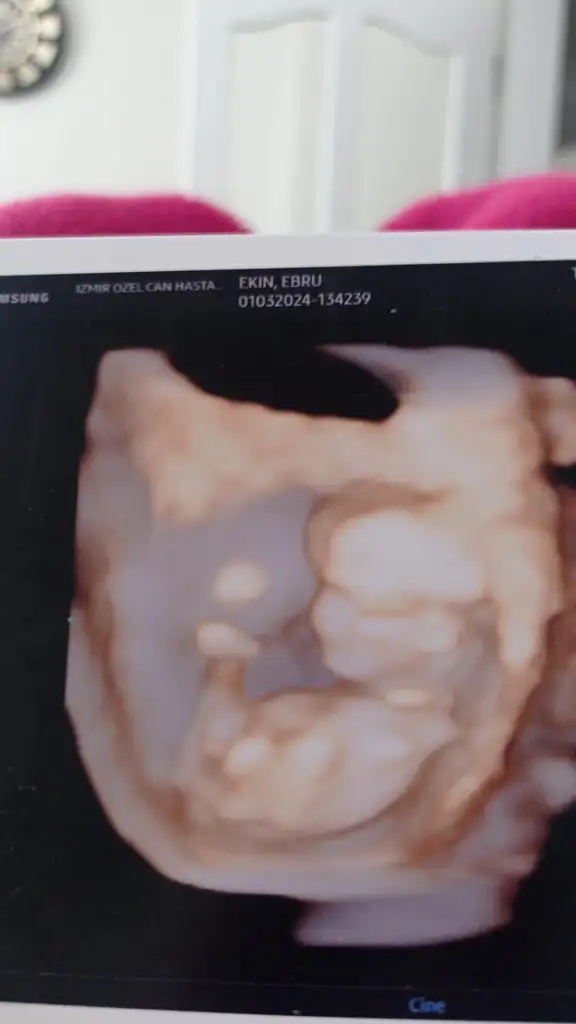

Kızlar sizce cinsiyet ne nuba göre herkez kız diyor kız olsa renkli ultrasonda bu kadar belirgin çıkıntı olurmu

Eklentiler

• IMG-20240418-WA0026.webp

IMG-20240418-WA0026.webp

13,8 KB · Görüntüleme: 88

• IMG-20240421-WA0000.webp

IMG-20240421-WA0000.webp

11,5 KB · Görüntüleme: 91

Fotoya tekrar baktım bence kız bu erkek olması için çizginin yatay değil dik olmasi lazım seni ki yatay gidiyor benim kide öyleydi doktor kız dedi inşallah gönlünden geçen olur

Çizgiden kastınız nedir acaba onu anlayamadım, kendime de bakacağım da :)